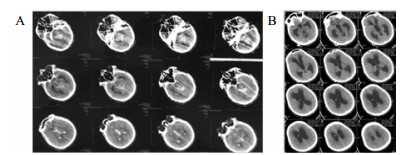

将分流管压力降为0.5后的第6天,该患者复查头颅CT和意识水平均无明显改变;后经分流储液囊穿刺脑脊液外引流,每日引流量150 mL,持续10 d,仍无明显改变。再将脑脊液外引流量增至300 mL/d,患者行为学稍有变化,开始出现刺激后头部转动、手部摸索活动,眼球能视觉追踪。复查头颅CT示脑室形态略缩小。因此,在此基础上再次手术将分流管由原来的抗虹吸可调压管更换为非抗虹吸可调压管,压力设为1.0。患者意识水平进一步改善,术后第4天复查CT示脑室较前缩小(图 2),其大小形态接近正常。随访一年,患者生活能自理,E-GOS 5分。

| 图 2 病例1更换分流管后第4天头颅CT |